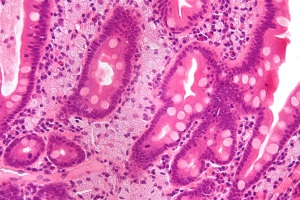

- Гастроентерологія

- Проктологія